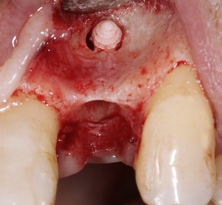

Der chirurgische Eingriff wurde unter Lokalanästhesie mit palatinaler und labialer Infiltration durchgeführt. Zuerst erfolgte die Entfernung des Implantats. Für die Explantation wählten wir das aus unserer Sicht knochenschonendste Verfahren. Mithilfe einer Extraktionszange und mit entsprechend dosierter Kraft drehten wir das teilweise ankylotische Implantat in Achsrichtung aus, um auf jeden Fall die dünne labiale Knochenlamelle zu erhalten (Abb. 3). Dabei frakturierte der osseointegrierte Implantatapex tief im Implantatbett (Abb. 4). Um diesen zu entfernen, musste ein minimalinvasiver apikaler Zugang geschaffen werden. Nach einer krestalen Inzision mit mesialer Tunnelpräparation und distaler Entlastungsinzision sowie der Präparation eines Mukoperiostlappens zeigte sich ein ausgeprägter konkaver Alveolarknochen. Mit einem piezotechnisch unterstützten Chirurgieansatz fenestrierten wir die labiale Knochenlamelle (Abb. 5). Durch diesen minimalinvasiven Zugang lösten wir die ankylotische Verbindung und entfernten den apikalen Implantatrest. Bei dieser Methode der Implantatentfernung wird der periimplantäre krestale Knochen weitestgehend geschont.